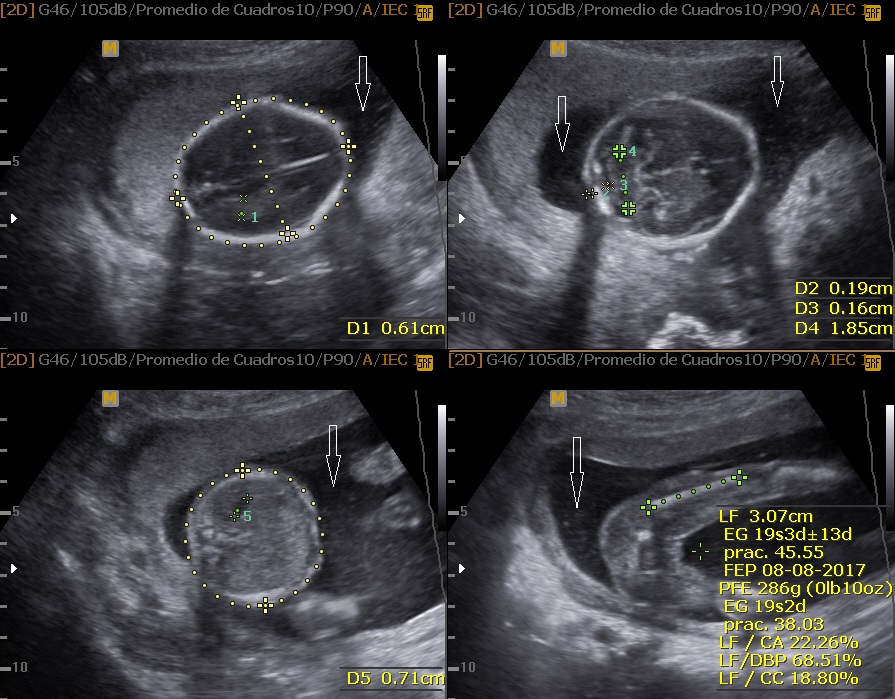

Maternofetal